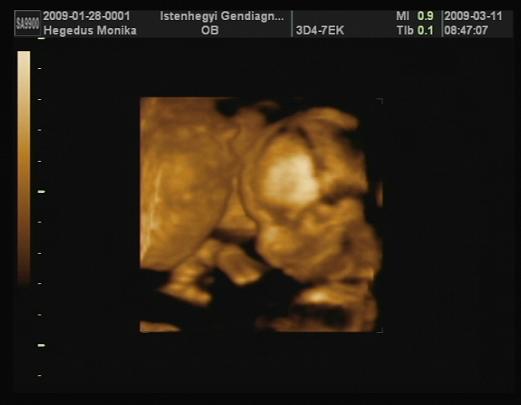

Az AFP-re azt mondták szó szerint,hogy nagyon tökéletes főleg ,hogy ráadásul lombikos a Bébike.

Az UH-t szintén így jellemezte ,hogy tökéletes a gyerek :D:D:D:D

18.5 cm hosszú ,235gr :D

Kiscsajunk van :D:D:D

Teszek fel képet :D

Kép

Sikerült a videóból kivágnom egy képet :D

Itt talán jobban látszik a jányom :D